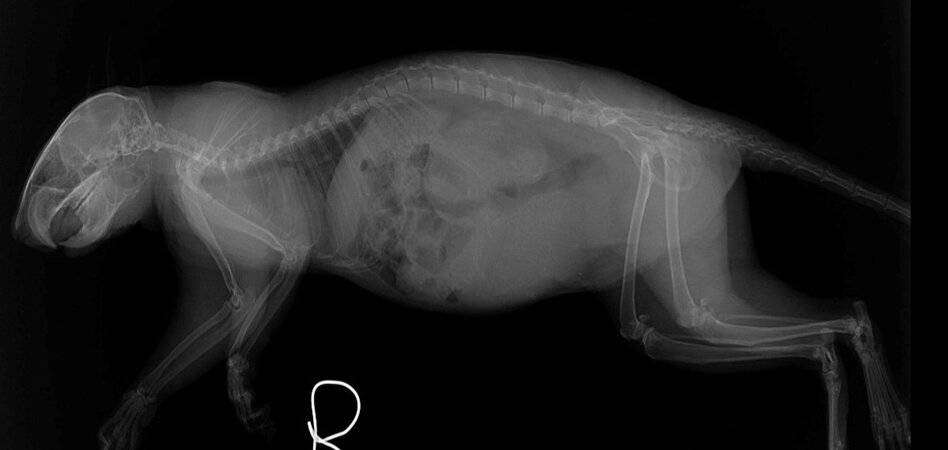

What do you see in this x-ray?

Did you notice that this squirrel is pregnant?! If you look closely at the x-rays, you can see the spines and skulls of her developing fetuses!